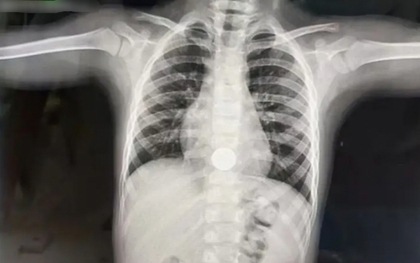

"Con kể mẹ nghe 1 bí mật" - Bà mẹ toát mồ hôi sau lời nói của đứa trẻ 3 tuổi, vội đưa con đi cấp cứu ngay trong đêm

Sau khi nghe lời tâm sự của con, người mẹ vô cùng hốt hoảng và phải đưa trẻ lập tức đến bệnh viện.